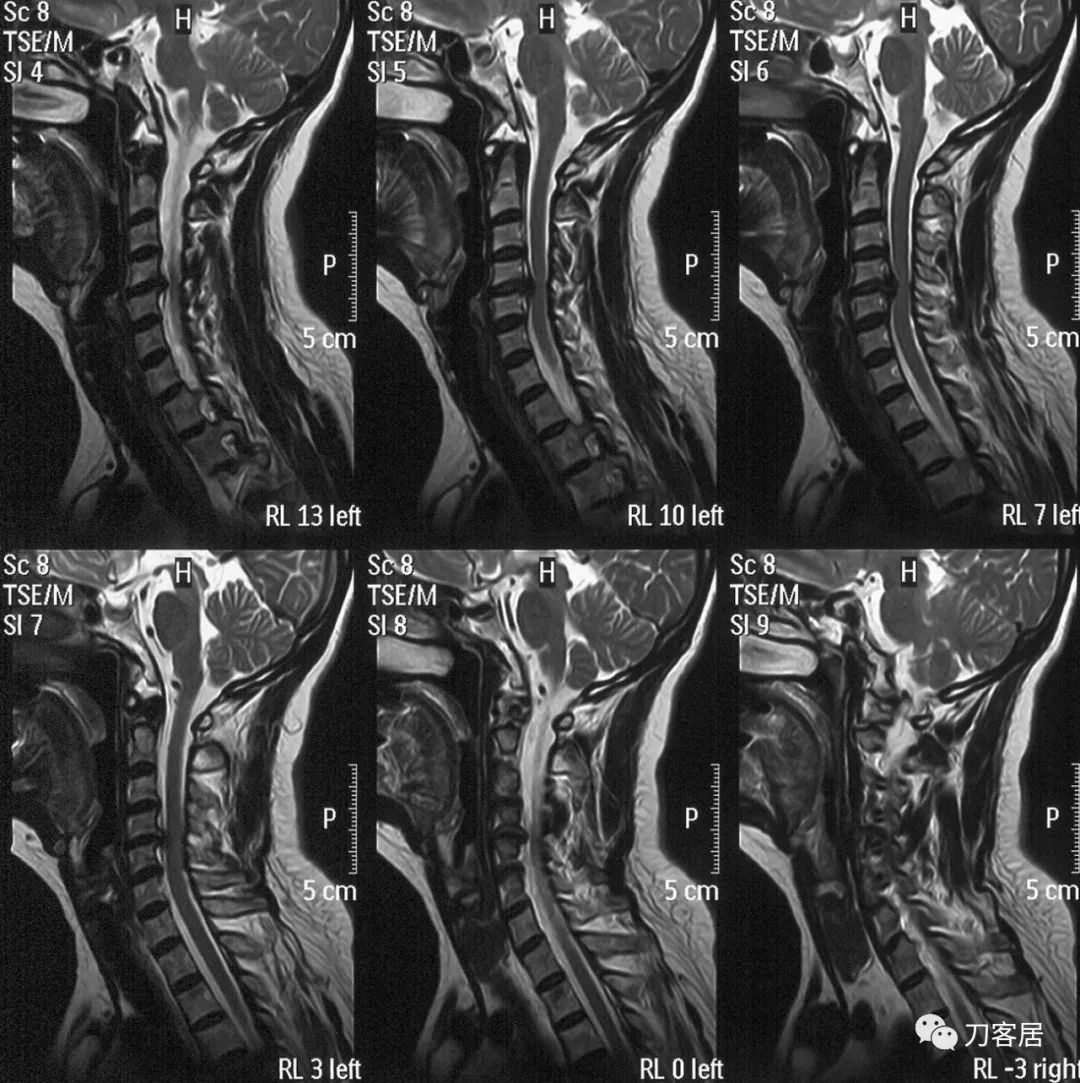

图2. 颈椎MRI矢状切面T2相提示颈4-5椎间盘突出,椎管狭窄,脊髓受压,脊髓变性

图3. 颈椎MRI矢状切面T1相提示颈4-5椎间盘突出,椎管狭窄,脊髓受压,脊髓变性